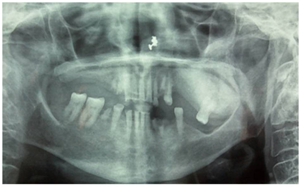

Intraorally, a diffuse expansile lesion involving the left maxillary posterior region, measuring approximately 40mmx30mm was extending from the distal aspect of 24 to the tuberosity region with partial obliteration of the buccal vestibule (Figure 1) and normal overlying mucosa. The swelling was non tender and bony hard in consistency. There was partial paraesthesia. 16,17,25,26,27,34,36 and 37 were missing, 11 and 21 were non vital along with generalized attrition. Based on the history and clinical examination, a provisional diagnosis of a benign lesion affecting the left maxilla was arrived at.

Figure 1 Partial obliteration of the buccal vestibule.